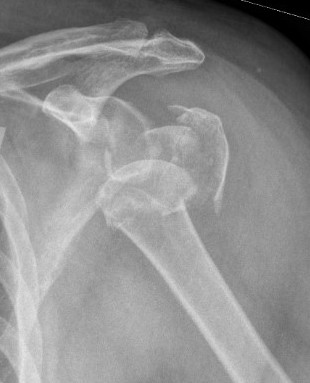

Severe comminuted proximal humerus fractures

100% displaced / off ended

Fracture - dislocations

- comminuted, 3 or 4 part

- head spltting fracture

- off ended / 100% displaced

Unreconstructable fracture - 4 part, comminuted, head spltting fracture